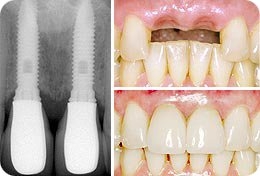

Zaujíma vás cena za prsné implantáty ? Dohodnite si konzultáciu s lekárom, ktorý vám zodpovie akékoľvek otázky a prezradí vám aj celkovú cenu za operáciu. K dispozícii sú guľaté implantáty , ktoré sa vkladajú pod prsnú žľazu alebo pod prsný sval, ale aj tzv.

Tiež som bol jedným z tých matiek, ktoré prišiel na dojčenie by sa jednoducho prísť prirodzene ku . Rozhodla jste se podstoupit plastickou operaci, která navrátí opět pěkný vzhled vašim prsům? Zajímá vás cena za prsní implantáty ? Sjednejte si konzultaci s lékařem, který vám zodpoví jakékoliv otázky a prozradí vám i celkovou cenu za operaci. Liečba jaziev injekčnou aplikáciou kortikoidu – ampulka. Zväčšenie prsníkov vložením okrúhlych implantátov (značky Eurosilicone) – cena je vrátane ceny implantátov , fixačnej podprsenky, hospitalizácie noc pod odborným dozorom a preventívnej . Bez ohľadu na to, či sa meníš na tú ženu, ktorou si chcela byť od narodenia, alebo len zdokonaľuješ svoj vzhľa aby si zvýraznila svoju krásu, Tvoje dobrodružstvo so zväčšovaním prsníkov bude pozostávať z troch etáp. Sme tu preto, aby si bez váhania prešla každou z nich!